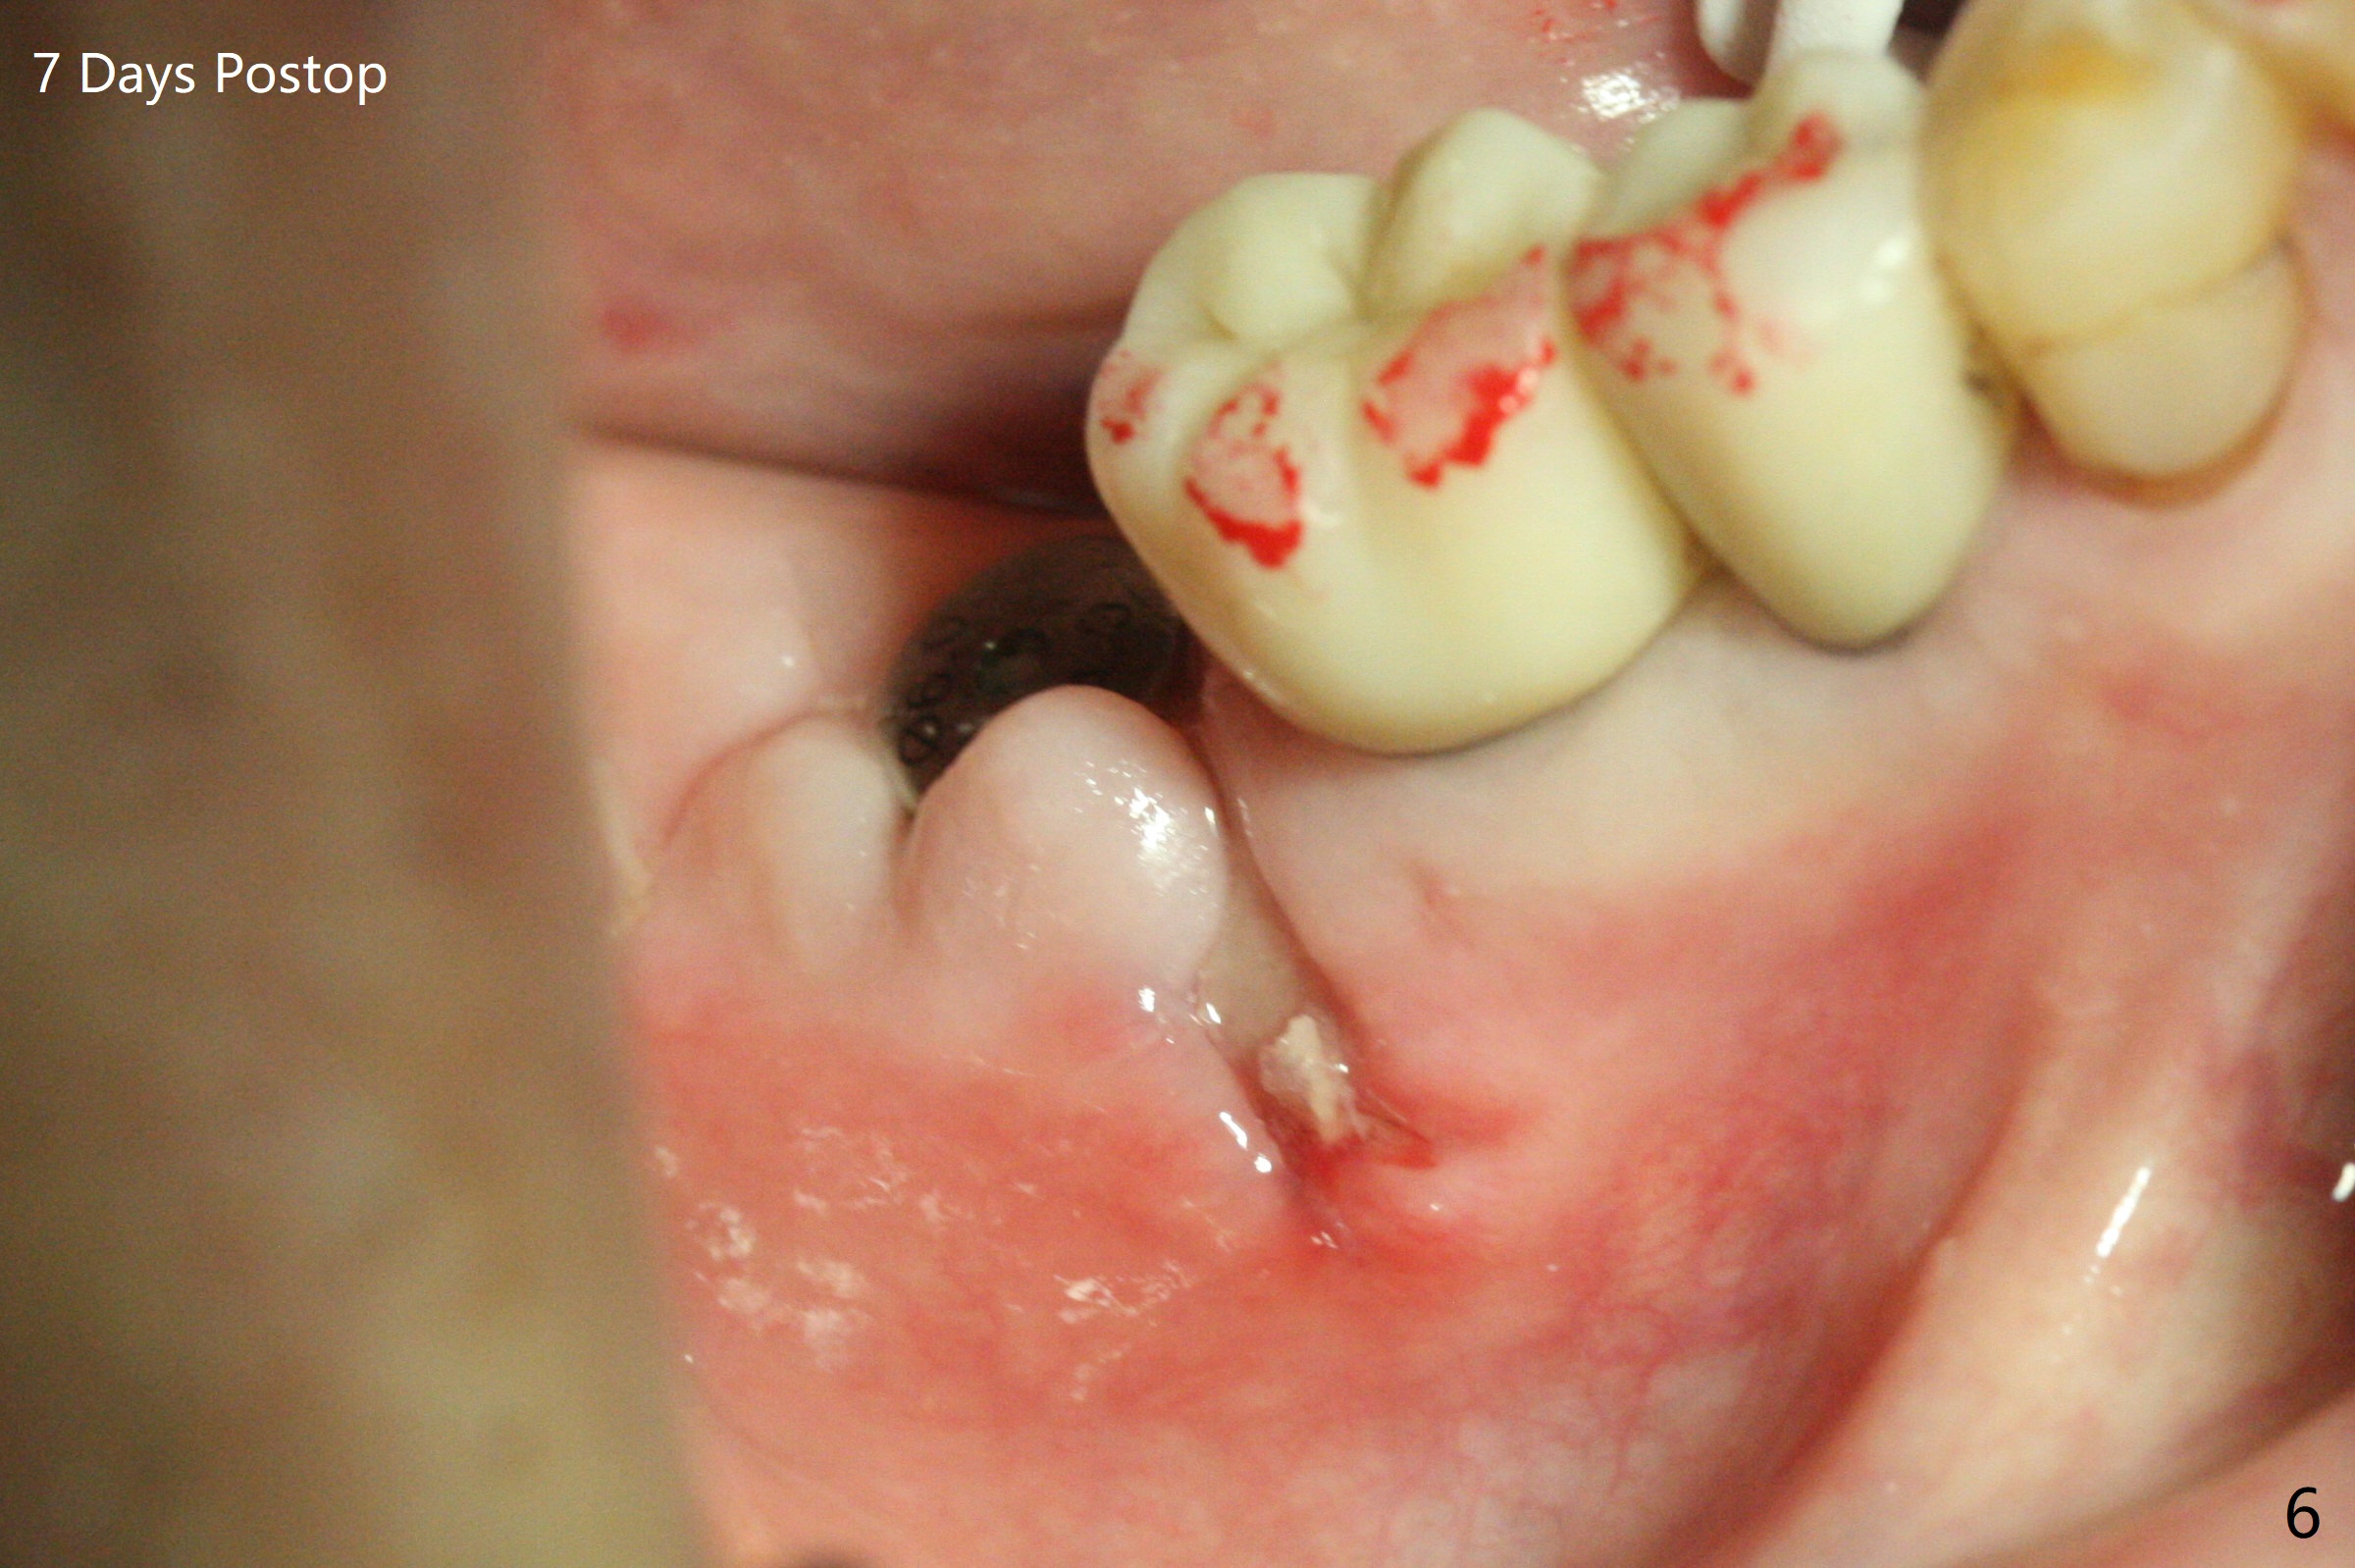

After 2.2x10 mm drill at #31 (Fig.1), bone expansion is conducted with 1.7/3.1 mm and 2.4/3.7 mm Expanders with guide (Fig.2) and 3.0/4.4 mm one without guide. Guided surgery resumes as planned to remove the lingual and apical bone. The buccal bone looks porous from the osteotomy opening. Mixture of autogenous and allograft is packed against the bone plate from the osteotomy before implant placement, but the 5x10 mm implant is unable to be seated completely. After removal of the bone graft from the osteotomy site and use of 4x11.5 mm drill for ~ 1 mm, the implant is seated with ~ 60 Ncm (Fig.3). With buccal incision, bone graft is placed over the distobuccal exposed implant thread (Fig.4 *) following placement of a 6x4 mm healing abutment. Oozing from the wound (thrombocytopenia) is controlled by Polysyn suture and perio glue (Fig.5). The mesial wound dehiscences 7 days postop when DO composite is placed at #28 (Fig.6). Two days later the patient returns because of hemorrhage in brushing. After placement of a taller healing abutment (6x7 mm) with triple antibiotic ointment (although the gingiva cuff is healthy), periodontal dressing is applied. Then the wound heals. The longer healing abutment remains seated (Fig.7 <) without interference from the crest (*) 4.5 months postop. A smaller cemented abutment (5.2x4(4) mm) is chosen with the same outcomes (well seated without gap (Fig.8 < between the implant and abutment), clearance from the crest (*)) 5 months postop. The final crown is cemented 6 months postop with distal access hole (Fig.9 black line), which may be related to design using normal 2nd molar tooth. In fact this patient has small teeth.